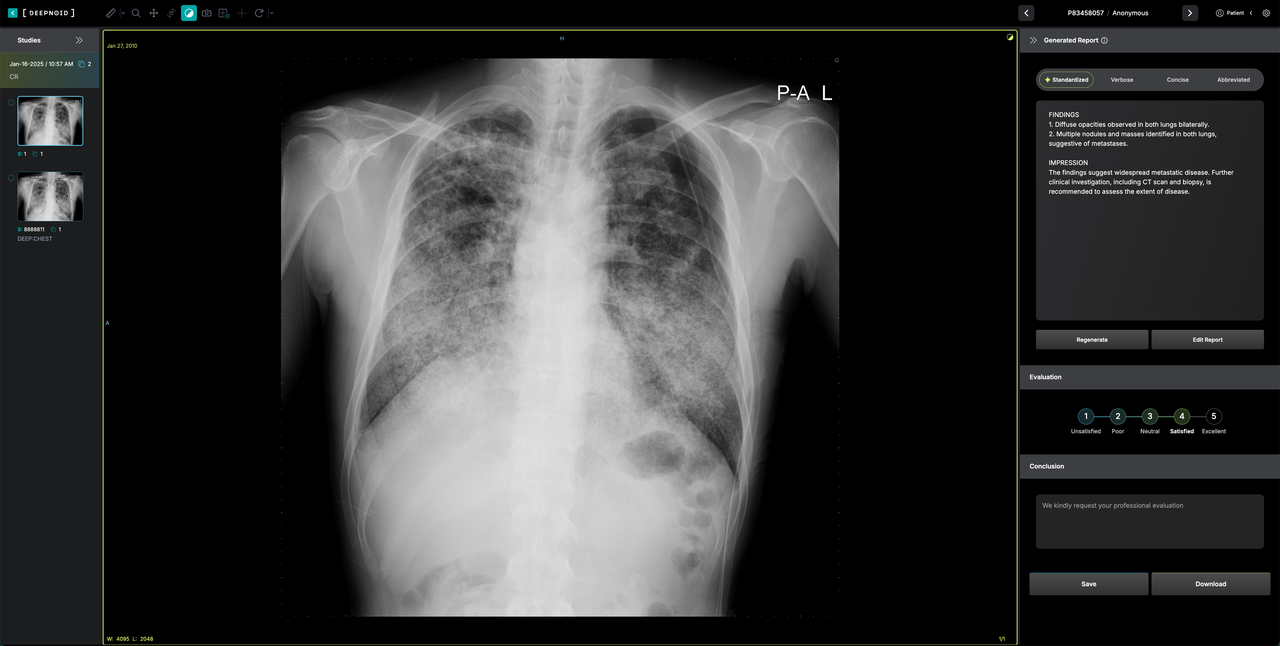

딥젠은 오픈 소스의 장점을 선택적으로 적용하는 의료 최적화 AI 서비스 플랫폼이다. 이번에는 강화학습(RL) 및 증류(distillation)의 장점을 가진 R1을 적용, 추론 및 생성의 정확도를 높였다고 설명했다.

R1이 적용된 딥젠은 적은 데이터만으로 최적의 의료 의사결정이 가능하다는 설명이다. 의료기관 특성과 환경에 맞춰 AI가 스스로 학습, 점진적으로 최적화하는 방식이다.

증류를 통해 병원마다 다른 IT 인프라 환경에서도 동일한 성능을 구현할 수 있다. 클라우드 환경이나 다양한 의료 기기 및 시스템에서도 빠르고 효율적으로 딥젠을 사용할 수 있다고 밝혔다.

유병철 딥노이드 수석연구원은 “이번 업그레이드를 통해 국내외 원격 판독문 서비스 시장을 선점할 계획”이라며 “향후 진료 지원, 질병 예측 등 AI 기반 의료 서비스를 확대해 나갈 예정”이라고 말했다.